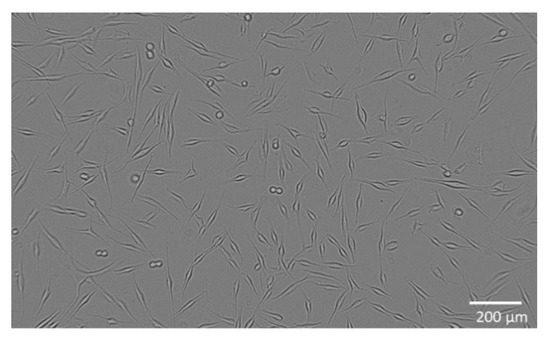

2.3. Metabolic Activity of WM-266-4 Cells and Appoptosis

4.5. Metabolic Activity of WM-266-4 and Normal Human Epidermal Melanocytes

4.6. Determination of Cell Apoptosis